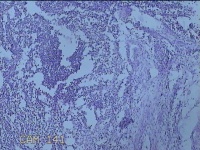

右侧会阴部结节

性别

女

年龄

31岁

临床诊断

皮脂腺囊肿

一般病史

发现右侧会阴部结节2个月。

标本名称

大体所见

灰白暗红色结节1.7x1.3x0.3cm一个,表面糜烂,切开结节呈实性,切面灰白暗红色,质软。